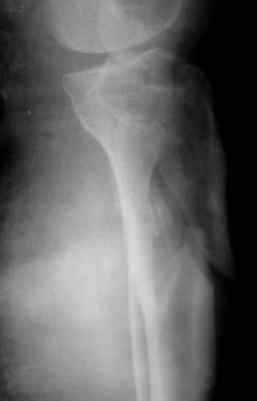

Мама 4 дня назад получила двойной перелом в голени

Диагноз такой:

1) Открытый перелом нижней 3-й большой берцовой кости

2) Верхней 3-й малой берцовой кости справа со смещением

Снимки смогли сделать только через 4 дня, я смогла приложить только 1 снимок к форуму

В пятку ей вставили штырь и повесили гирю сразу.

Есть возможность сделать операцию и вставить титановую пластину.

Проконсультировались с другим врачом-травматологом, он говорит, что при таком переломе нужен аппарат Илизарова. И делать нужно как можно скорее.

А наш врач говорит, что в ноге, так где кость проткнула кожу есть инфекция, сейчас ей обрабатывают марганцовкой и назначили кварцевание. Врач назначил операцию по вставлению тинановой пластины только через неделю, ссылаясь на инфекцию. Говорит, что если делать сейчас мы сможем ее занести внутрь на 80%, а он на себя такую ответственность брать не собирается. Говорит там пузырь и только когда кожу залечим, будем делать операцию

Другой врач говорит, что важно сделать операцию сейчас, а кожу залечить потом